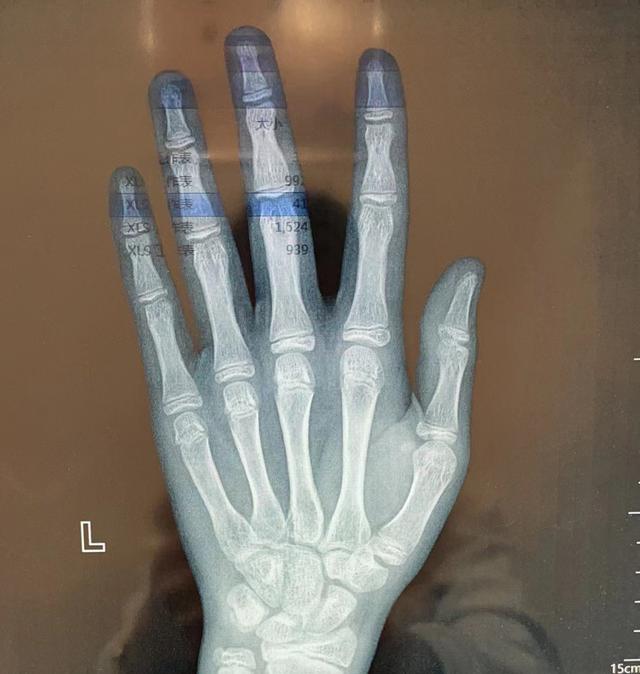

尺骨茎突不明增生···尺骨茎突撞击综合征?

图片尺寸2448x3264